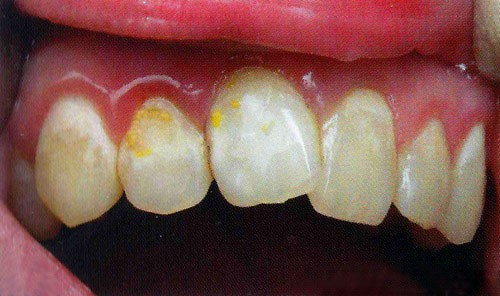

На фотографии зубы с кариесом в стабилизированной форме – наличие темных, светло-коричневых или бурых пятен.

Кариес в стадии пятна разделяют на активную и стабилизированную формы. Для активной формы кариозного поражения характерно наличие белых (меловых) пятен на поверхности пораженного зуба, стабилизированная форма кариеса характеризуется наличием темных, светло-коричневых или бурых пятен.

Своевременное лечение начальной стадии болезни, заключающееся в проведении реминерализующей терапии, позволяет устранить меловые пятна и полностью устранить дефект эмали. Если пятно находится в стабилизированной стадии, то есть уже потемнело, то реминерализующая терапия не позволит устранить данный дефект. Стабилизированная форма требует искусственного восстановления эмали, то есть пломбирования.

Следует отметить, что стабилизированная форма кариеса в стадии пятна относится к медленно прогрессирующим формам кариозного поражения, следовательно, кариозное пятно длительный период времени остается стабильным и не трансформируется в кариозную полость. При отсутствии клинических показаний такое пятно требует постоянного контроля, к его препарированию и последующему пломбированию приступают только в том случае, если кариозное поражение активизируется или покрывает более 1/3 поверхности зуба.